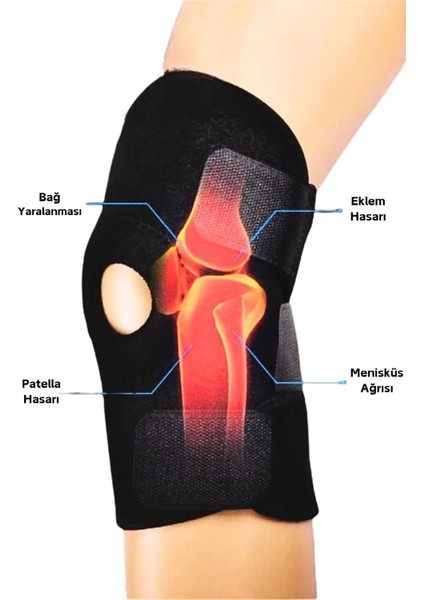

Denisam Diz Korsesi Çapraz Bağ Menisküs Ağrısı Için Dizlik Diz Bandajı Patella Dizlik

Diz Korsesi Çapraz Bağ Menisküs Ağrısı Için Dizlik Diz Bandajı Patella Dizlik